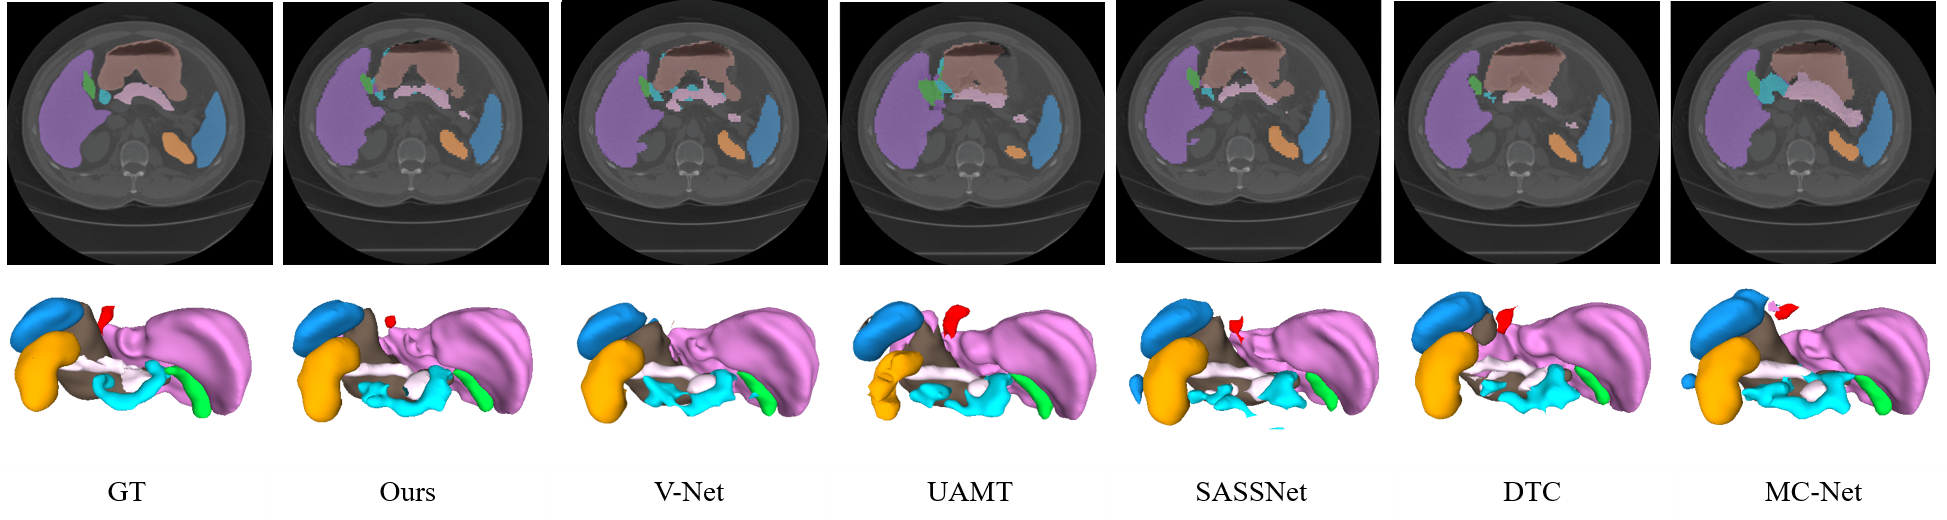

Abdominal multi-organ dataset To prove the effectiveness of our method on a multiclass dataset, we conducted an experiment on an MO dataset. For comparison, several state-of-the-art models (i.e., UA-MT[10], SASSNet[13], DTC[11], and MC-Net[12]) and the base network, VNet, were used for evaluation. We considered 20% of training data among the 70 images as the labeled data (14 labeled) and the others as unlabeled data (54 unlabeled). All the models used VNet as their backbone network. Table II presents quantitative comparisons of the segmentation results. The results indicate that our method outperforms the other methods in terms of all evaluation metrics (i.e., Dice (71.28%), Jaccard index (59.01%), HD (4.32), and ASSD (1.24)). Our method achieves significant improvements in the segmentation of spleen, liver, stomach, and pancreas and demonstrates competitive results for other organs. A box plot for a more precise quantitative comparison is presented in Fig. 4. The qualitative results illustrated in Fig. 6 indicate that our method segments multiple organs better than other methods.